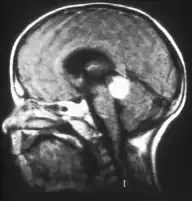

Aspect of trilateral retinoblastoma on MRI

Inherited forms of retinoblastomas are more likely to be bilateral. In addition, inherited uni- or bilateral retinoblastomas may be associated with pineoblastoma and other malignant midline supratentorial primitive neuroectodermal tumors (PNETs) with a dismal outcome; retinoblastoma concurrent with a PNET is known as trilateral retinoblastoma.[17] A 2014 meta-analysis showed that 5-year survival of trilateral retinoblastoma increased from 6% before 1995 to 57% by 2014, attributed to early detection and improved chemotherapy.[18]

In about two-thirds of cases,[29] only one eye is affected (unilateral retinoblastoma); in the other third, tumors develop in both eyes (bilateral retinoblastoma). The number and size of tumors on each eye may vary. In certain cases, the pineal gland or the suprasellar or parasellar region (or in very rare cases other midline intracranial locations) is also affected (trilateral retinoblastoma). The position, size, and quantity of tumors are considered when choosing the type of treatment for the disease.